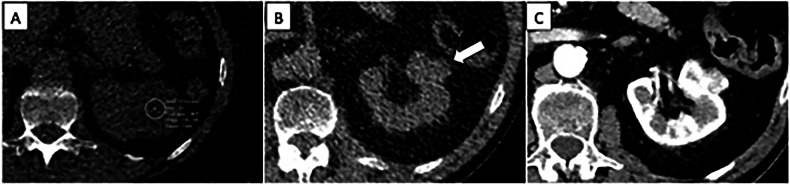

Based on NLST data, over 20% of the deaths in the LDCT arm were attributed to extrapulmonary cancers (including mediastinal, liver, pancreatic and kidney cancers), with renal and liver lesions being the most frequently reported significant IFs (Fig. 1) [11]. With the evaluation of subdiaphragmatic organs being only partial, chest LDCT cannot be considered a technique that provides a reliable assessment of extrathoracic organs. In the NLST, there were more individuals diagnosed with kidney, thyroid and liver cancers in the group without reported potentially significant findings [27]. Only a very small proportion of IFs are malignant: reported rates of extrapulmonary malignancies incidentally detected during LCS range from 0.05% [28] to 0.5% [27, 29, 30]. There is no scientific evidence on whether the early diagnosis of these malignancies will reduce mortality, morbidity and the economic burden associated with managing cancers at advanced stage [31].

Fig. 1.

Challenges associated with the characterization of renal lesions. A Hypoattenuating lesion of the left kidney whose cystic or solid nature cannot be assessed due to a large deviation in attenuation measurement. B Exophytic lesion of the left kidney with high attenuation (white arrow); the extrathoracic IF was reported and evaluated by contrast-enhanced CT (C), which confirmed a lesion representing a stage I clear cell renal cell carcinoma. The detection of such a small exophytic renal lesion was due to a very attentive image review: in the setting of LCS, it can be debated if it should be considered a missed diagnosis if unmentioned